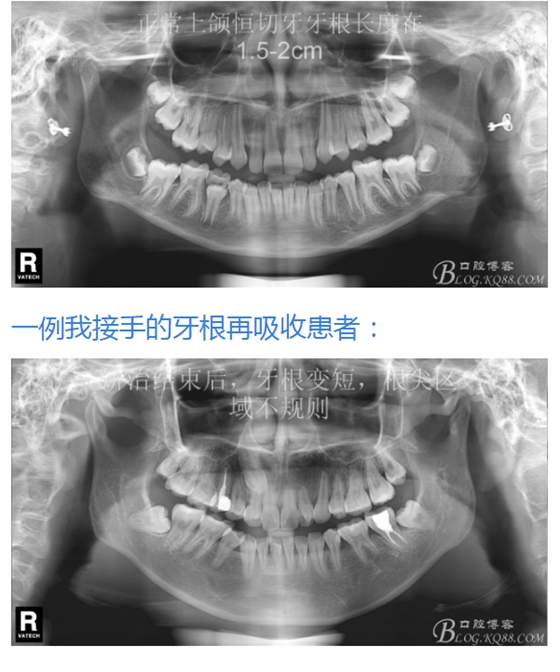

有15%的人在正畸治療前就已經(jīng)發(fā)生牙根吸收,這與激素失衡和飲食缺乏有關(guān)。正畸治療后12個月,牙根再吸收的發(fā)生率增加到73%,有25%的正畸治療患者根尖吸收超過2mm,約5%的人發(fā)生超過5mm的嚴(yán)重吸收。

大多數(shù)研究認(rèn)同牙根再吸收的嚴(yán)重性與正畸治療的持續(xù)時間、力量大小相關(guān)。臨床醫(yī)師應(yīng)該采用輕力、高效的矯治手段進(jìn)行正畸治療,并在正畸治療前、中、后進(jìn)行X線檢查對比,觀察牙根再吸收的發(fā)生情況。研究發(fā)現(xiàn):間斷治療的患者其牙根再吸收量明顯少于那些持續(xù)治療的患者。應(yīng)用力的中斷有助于已破壞的牙周組織重建并減少牙根的進(jìn)一步縮短。